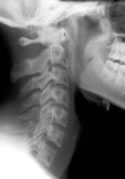

Identifying these ligamentous injuries, however,  can be difficult. The ligaments themselves may be detected on MRI, but they  cannot be seen on normal radiographs. It is more likely that the ligament  injury will result in changes to the alignment of the cervical spine, and that can be detected with plain films.

A 2002 study1 compared the angle of cervical lordosis between whiplash patients and healthy controls. They found a statistically significant difference between the two groups, suggesting that whiplash injuries may indeed alter cervical spine alignment.

The authors of this current study began with 13  patients who had been in a car crash. They obtained a neutral cervical  radiograph taken in the natural standing position. Then, each patient was  treated by a chiropractor. The patients had an average age of 24, and the  average number of chiropractic adjustments was 17.7.

After a period of care, neutral radiographs were again taken, and both the pre- and post-treatment films were evaluated by a second chiropractor who was blinded to which films belonged to which patient.

The cervical curve was measured in each of the x-rays.

10 of the 13 patients showed an increase in the cervical lordosis found on x-ray. The average increase found in the patients was 6.4°.

One patient showed no change and two patients showed a decrease in cervical lordosis.